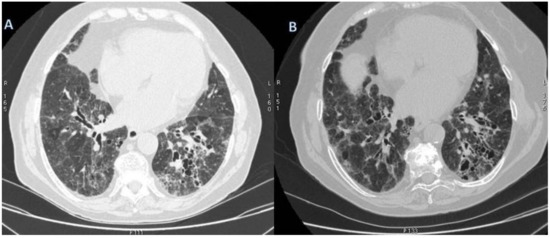

2.10. ILD in ANCA-Associated Vasculitides

2.10.2. Morphological Patterns and Imaging